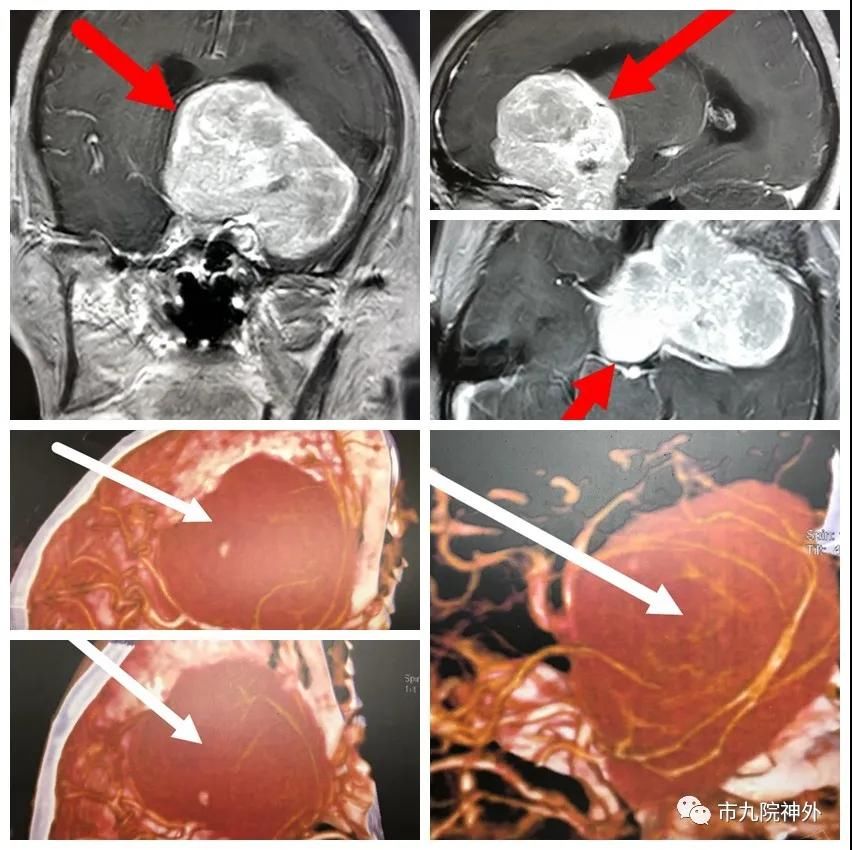

66岁患者李某,以视力下降1年,行走不稳1天之主诉入院。1年前曾在外院就诊,初以为视力退化,未作特殊处理,近日当地医院头颅CT示:颅内肿瘤。故来院要求手术治疗,住院后行MRI、CTA等检查,诊断为左侧蝶骨嵴巨大脑膜瘤。直径约7cm,与周围颈内动脉、大脑中动脉、大脑前动脉、双侧视神经黏连,肿瘤血运非常丰富。

科主任刘展会主任医师组织全科进行讨论:手术难度大。1.术中出血很大,随时有失血性休克,必须大量备血;2.术中注意分离颈内动脉及其分支和视神经,否则术后出现脑梗塞;3术中注意保护周围脑皮层,以防术后出现失语;4.术中肿瘤质地坚韧,切除困难,手术时间很长。

家属了解风险并同意后,刘展会主任、张睿副主任医师、豆涛涛医师在全麻下行颅内肿瘤切除术,术中在显微镜下经过二十小时的仔细分离,保全了颈内动脉、大脑中动脉、大脑前动脉、双侧视神经,严密止血,减少出血量,历经二十小时手术患者未出现休克。术中发现肿瘤质地坚韧,周围组织粘连严重,故选择分块切除肿瘤。术后病人恢复良好,神志清楚,四肢活动好,语言流利,未出现并发症。